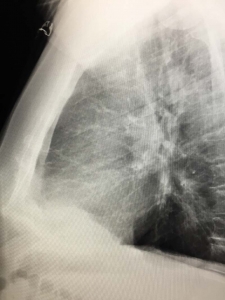

Mass in the lung on X-ray

A mass in the lungs on X-ray is seen as a white area greater then 3 centimeters in the normally dark lung. Many but not all masses will be seen on chest X-ray.

Most masses found on chest X-ray will be further evaluated with a chest CT. This is because most masses on chest X-ray will look the same regardless of the cause. A chest CT may help us make a diagnosis.